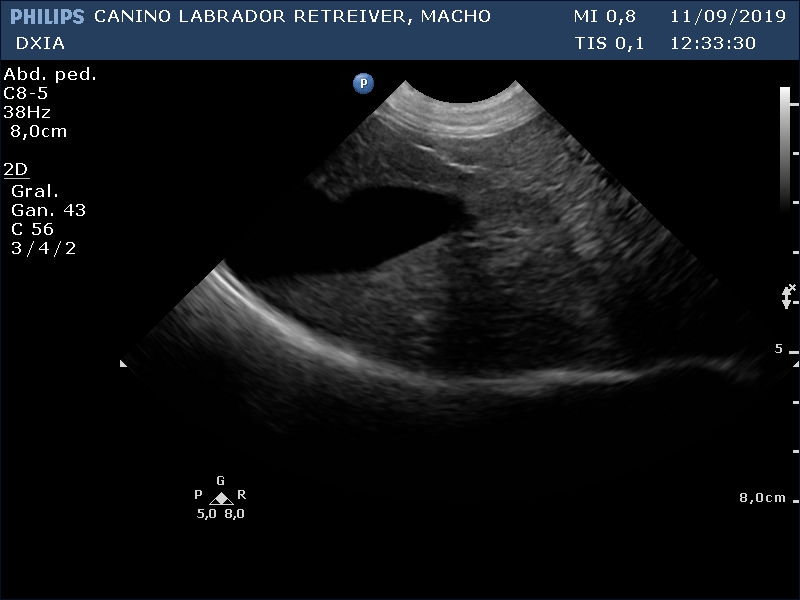

Revisión Imagen Hígado DXIA Scoot

Revisión Imagen Hígado a mitad de quimio